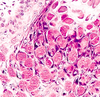

What is this histology ?

Viral Whart

Hyperkeratosis, Papillomatosis, Hypergranulosis

Vacuolated keratinic nucleocytes with pknotic raisen nuclei